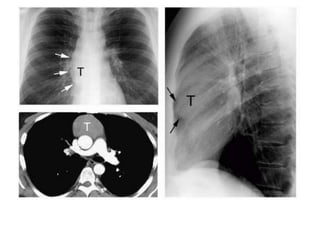

Posteroanterior chest radiograph shows a mass (arrow) obliterating

the posterior junction line. Note that the mass extends above the

level of the clavicle and has a well-demarcated outline due to the

interface with adjacent lung (arrowhead).

CT scan helps confirm the posterior location of the mass (arrow),

which proved to be a bronchogenic cyst.